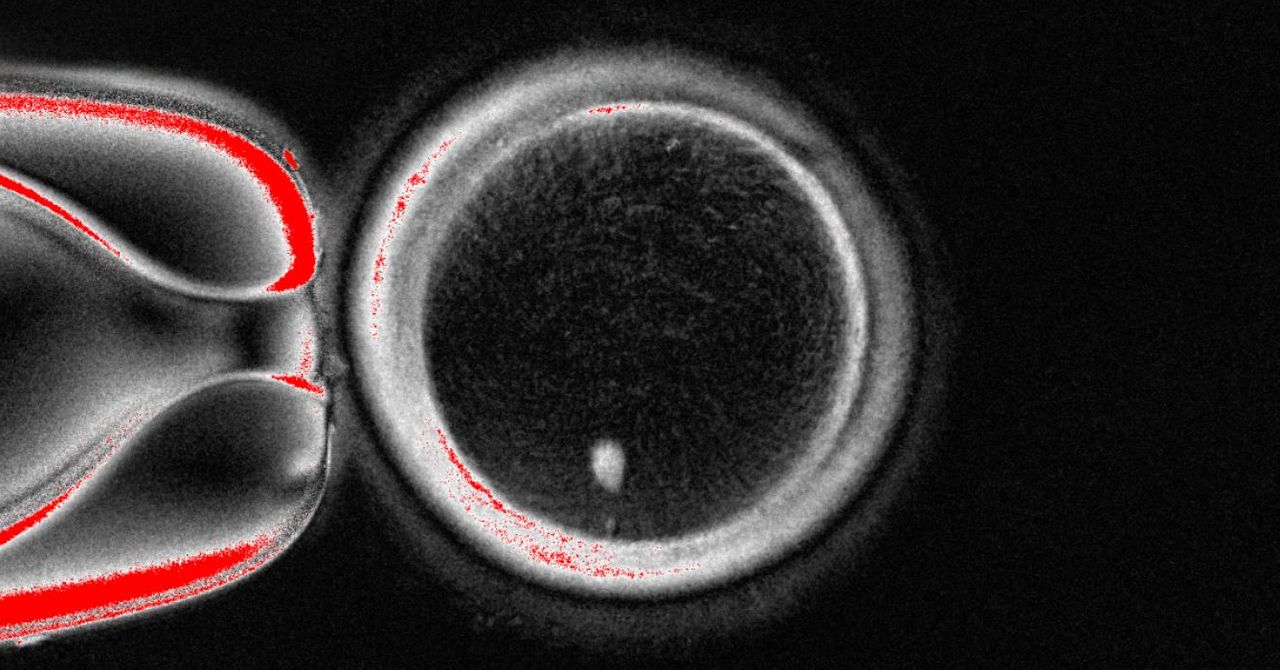

اولین بار در سال ۲۰۱۸، میتینوری سایتو از دانشگاه کیوتو، چگونگی تبدیل سلولهای خونی انسانی به سلولهای بنیادی و سپس تبدیل آنها به تخمکهای انسانی را مستند کرد. با این حال، این تخمکها به حدی نابالغ بودند که قابلیت بارور شدن و تشکیل جنین را نداشتند.

دانشمندان در حال پیشبرد مرزهای علم در حوزه تولیدمثل هستند و خبرهای امیدوارکنندهای از ساخت تخمک انسانی در آزمایشگاه منتشر شده است. این دستاوردها، در حالی که نویدبخش راههای جدیدی برای درمان ناباروری و درک بهتر زیستشناسی تولیدمثل هستند، سوالات مهم اخلاقی و اجتماعی را نیز مطرح میکنند.